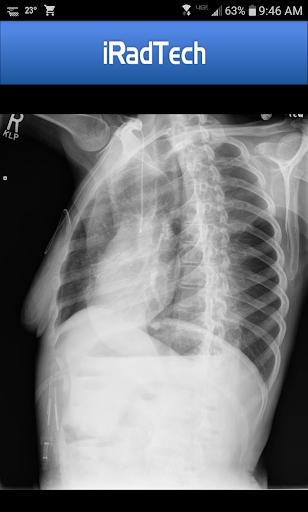

The app provides technical factors, image receptor specifications, patient positioning guidance, respiration instructions, and precise central ray details. It also features representative radiographic images that can be enlarged for better inspection, ensuring accurate positioning and image quality.

One standout feature is the enlargeable photographs of properly positioned human models, clearly showing the collimated area with central ray entry points. Additionally, each position contains a helpful NOTE tab where users can save techniques or other relevant information.

iRadTech's representative radiographic images and properly positioned human model photographs further support teleconsultation quality. These enlargeable visuals help practitioners verify correct positioning and collimation, leading to better communication and understanding between healthcare providers and patients.